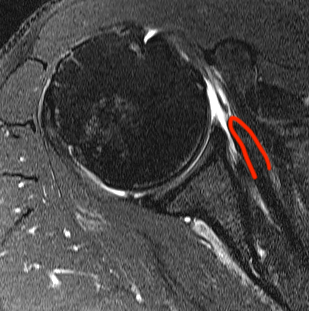

Perched long head of biceps with tear of upper border of subscapularis

Full thickness minimally retracted subscapularis tear